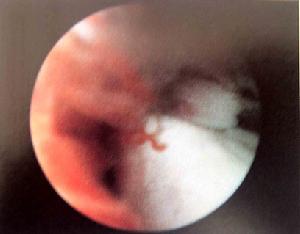

膝關節鏡檢查沖淨積血,可見ACL斷裂端出血或小血塊凝集。滑膜下韌帶損傷在關節鏡下貌似正常,但其長度及張力異常可提示本損傷的可能性。膝關節X線檢查,可顯示脛骨髁間隆凸骨折,內外應力檢查時可見一側關節間隙加寬。

4、膝關節鏡檢查。